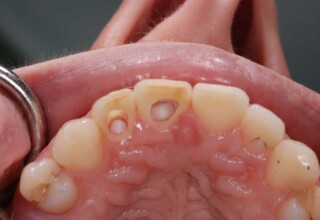

A rare case of dark root canal teeth with additional external absorption on the central incisor. After removal of the affected tissues of the central incisor, the tooth could not be directly bleached because of the soft tissue contact. The tooth was initially restored to provide the original tooth form, then it was bleached and the restoration was finalized.

Initial appearance

Final appearance